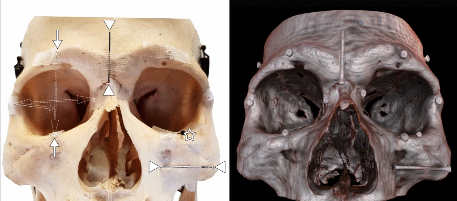

July 22, 2020Virtual reality orbitometry bridges digital and physical worldsA study validates the ability of virtual reality (VR) to provide similar quantitative data in ophthalmology and beyond as physical measurements, alongside the added benefit of VR interfaces.